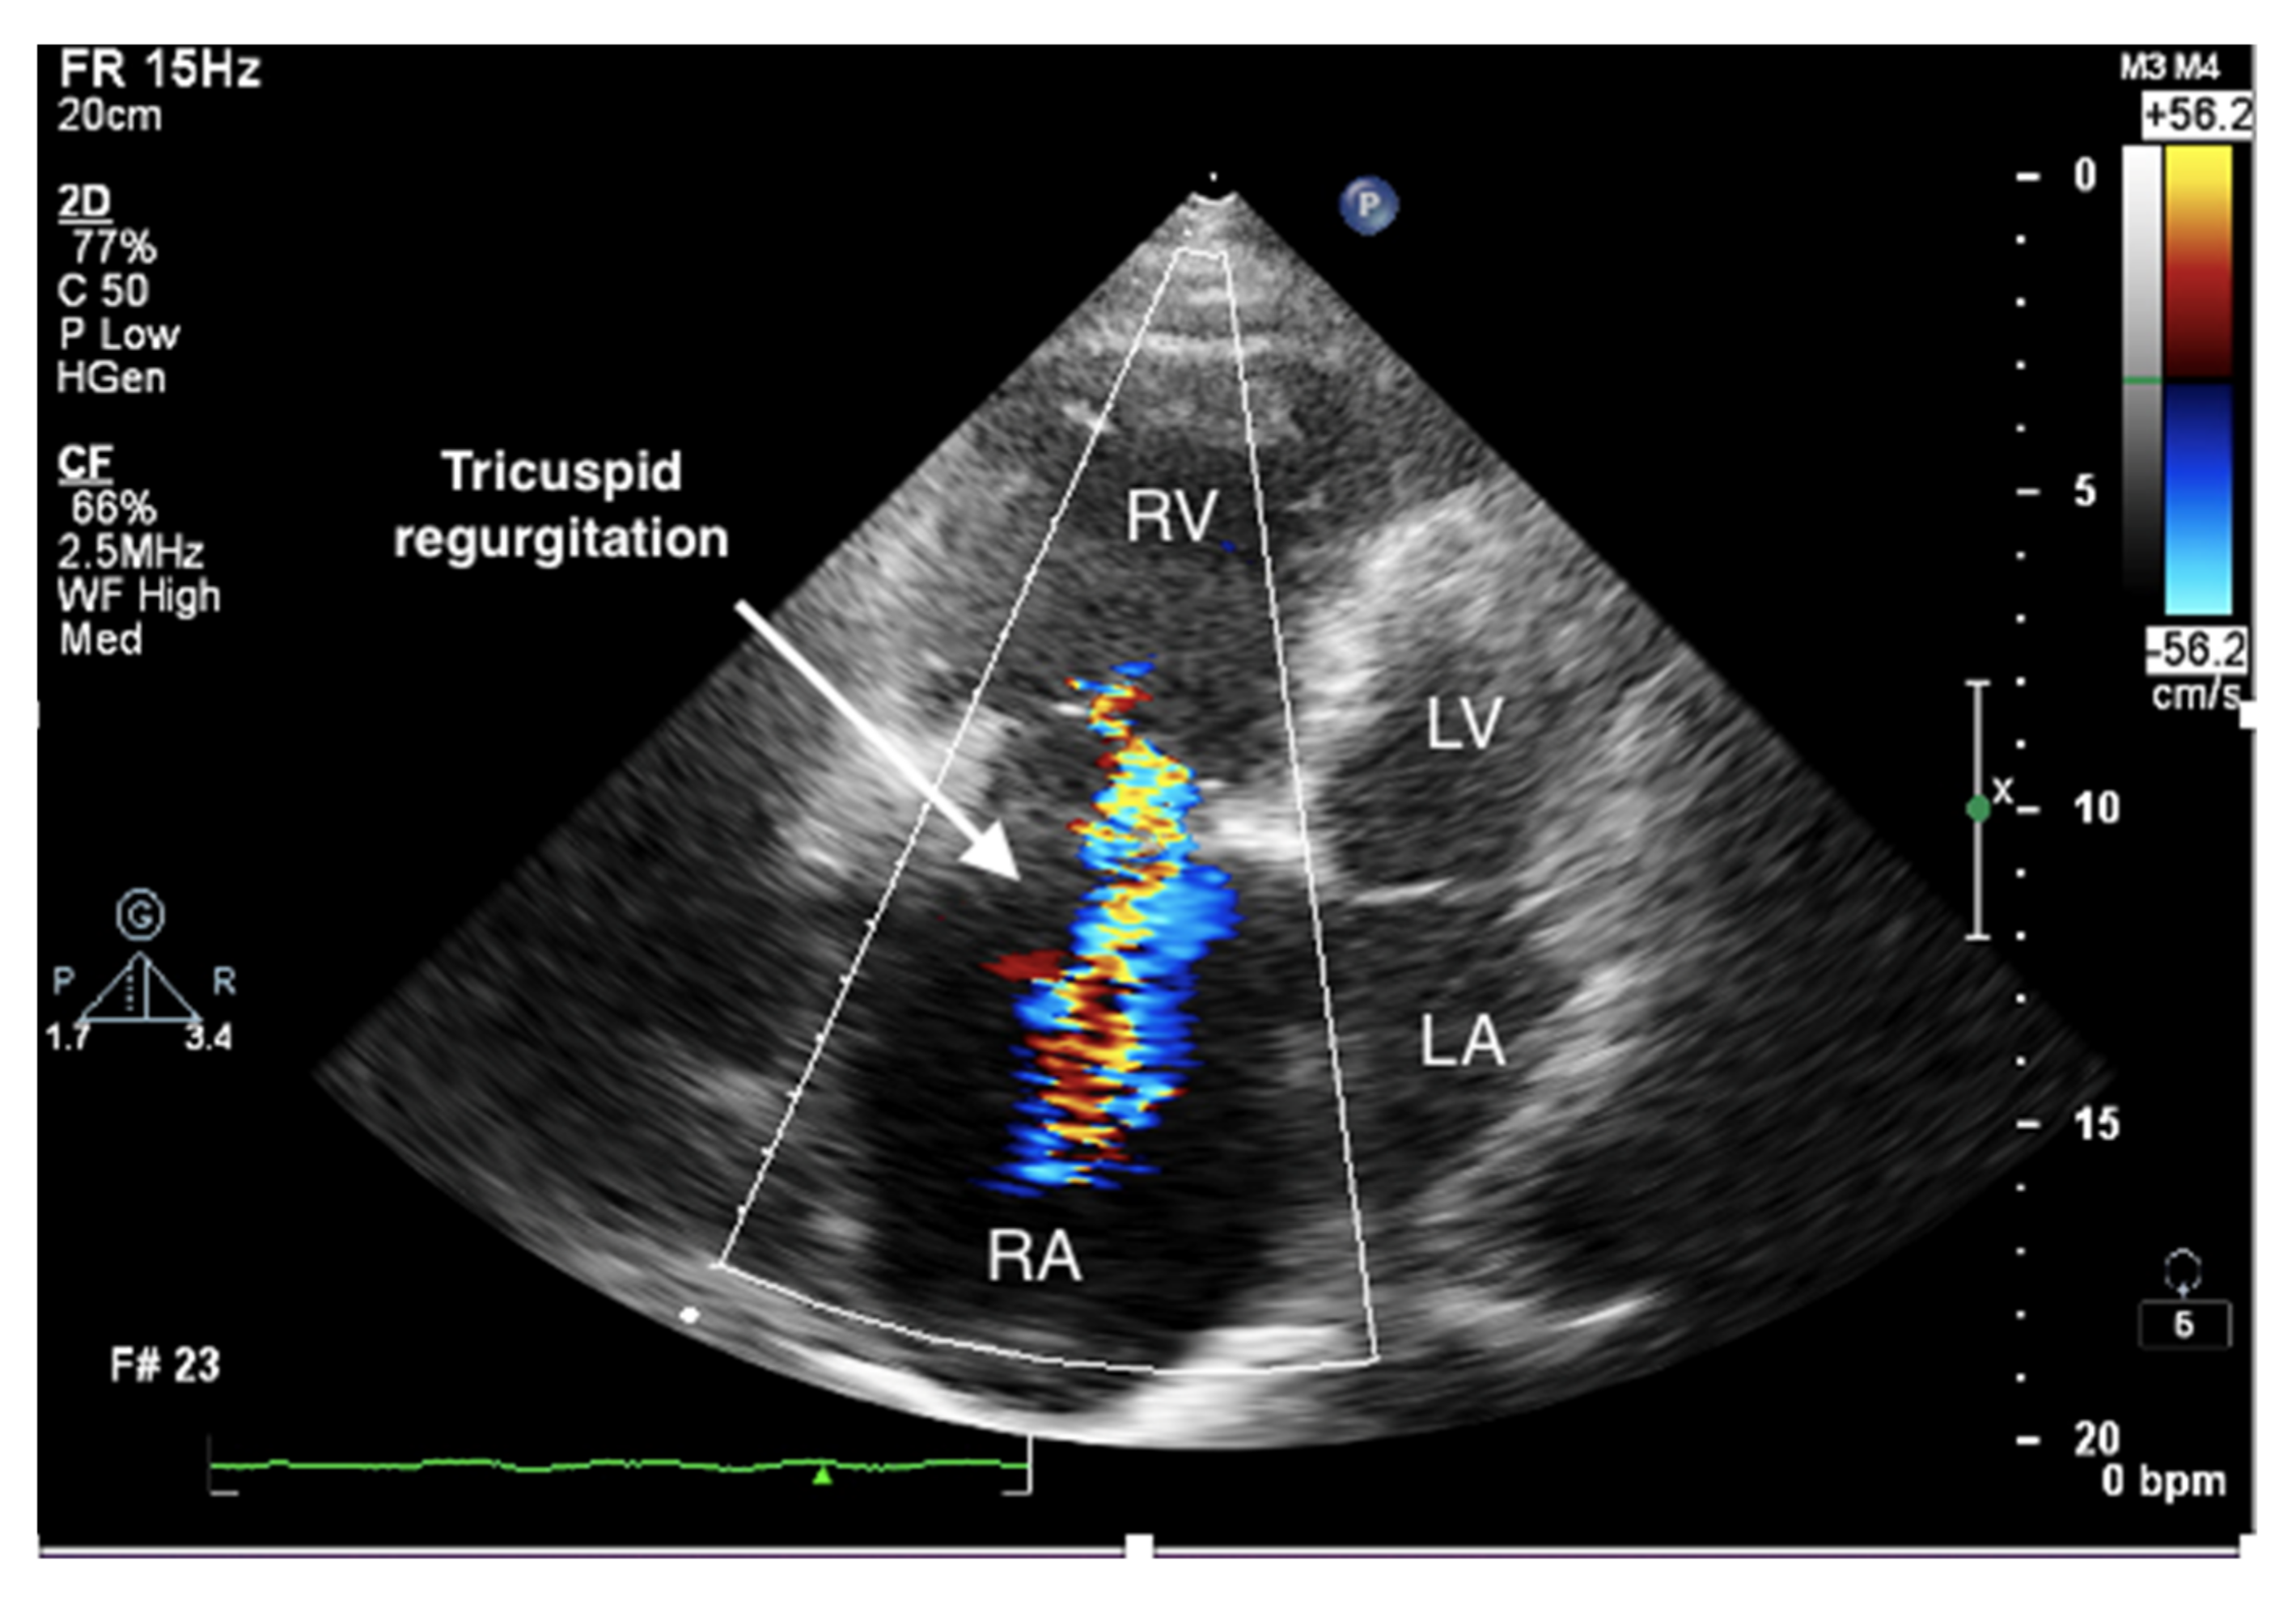

Figure 4.

Enlarged right ventricle and right atrium. Tricuspid regurgitation. 2D-TTE, RV-focused apical 4CH view.

It is believed that if there is no RV outflow tract stenosis, the right ventricular systolic pressure (RVSP) is equal to the pulmonary artery systolic pressure (PASP) [70]. In everyday practice, the calculation of PASP is based on a simplified Bernoulli equation applied to peak tricuspid regurgitation velocity (TRV). TRV should be measured in several views, aiming at the best image quality and maximum velocity in continuous-wave Doppler and avoiding excessive gain and artifacts (Figure 12 and Figure 13). According to the equation, PASP = 4 (TRV)2 + RAP [71,72]. In addition, based on the measurements of end-diastolic pulmonary regurgitant return wave velocity (PRVend), it is possible to estimate pulmonary artery diastolic pressure (PADP) using the PADP = 4 (PRVend)2 + RAP formula [73]. On the other hand, PASP and PADP values can be used to calculate approximations of mean pulmonary artery pressure (mPAP) using the mPAP = 1/3 (PASP) + 2/3 (PADP) formula [74]. Several other formulas for calculating mPAP can be found in the literature. Chemla et al. developed another method to calculate mPAP, according to the formula mPAP = 0.61 × PASP + 2 mmHg [75].

Figure 13.

Doppler assessment of tricuspid regurgitant velocity (TRV). Differential rate of tricuspid regurgitation wave jets in atrial fibrillation. TTE, 4CH view. TTE: transthoracic echocardiography; 4CH: four-chamber.